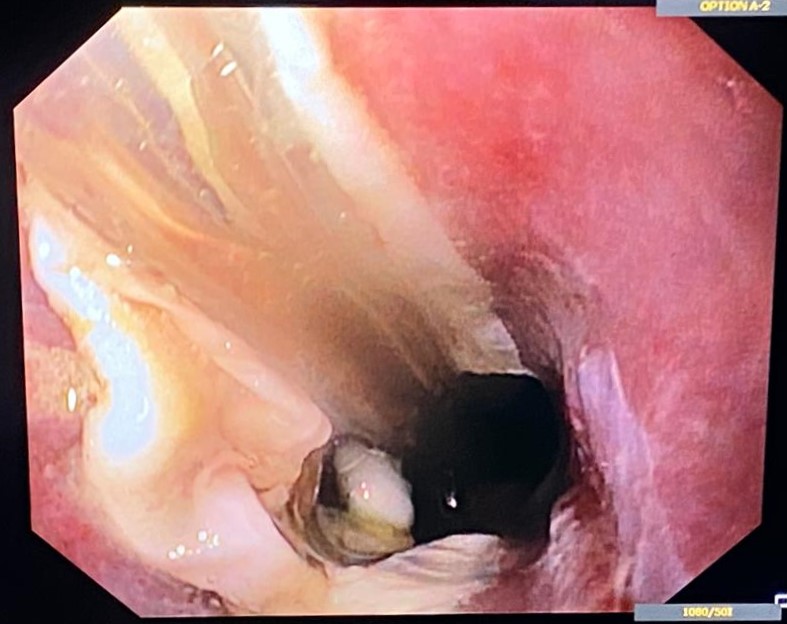

An unexpected esophageal finding: esophagitis dissecans

Diana Ramos1, Rui Morais2, Guilherme Macedo2

1 ULS Castelo Branco; 2 Centro Hospitalar do São João

A 57-year-old male was admitted to the intensive care unit with covid-19 infection, requiring invasive ventilation. Gastroenterology support was requested due to difficulty in placing a nasogastric tube, with a sensation of esophageal obstruction.

Upper endoscopy showed, at the level of the middle esophagus, whitish crepe-paper-like plaques that formed a pseudo-plug. After adequate distension, the lumen was permeable and longitudinal white plaques were adherent to the mucosa and were easily detachable, with the underlying mucosa being hyperemic. Biopsies revealed esophageal mucosa with inflammatory infiltrate, erosion and parakeratosis, confirming a diagnosis of esophagitis dissecans superficialis.

An unexpected esophageal finding: esophagitis dissecans

Fotografia